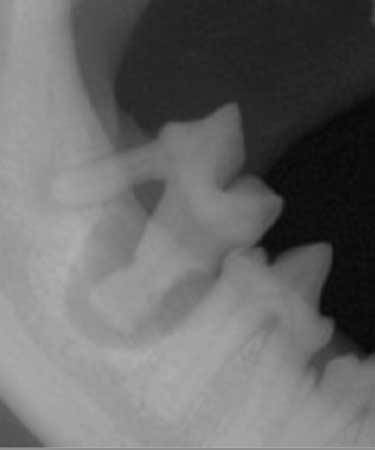

レントゲン検査

多くの口腔疾患は身体検査では把握できない歯内(歯髄)や下顎内(歯根や歯槽骨)に問題を抱えています。

そのため身体検査だけでは口腔疾患の診断や治療方針を誤ってしまう可能性があります。

よくある歯周病にしても、レントゲン検査で歯の根尖部、歯髄腔、歯槽骨の状態を確認することで、根管治療などの歯を残す治療が可能なのか、抜歯処置が必要なのかを見極めることができます。